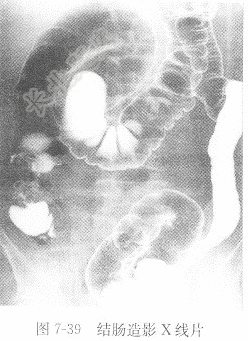

试题详情单项选择题男性,60岁,腹痛、腹胀3月,大便带血1个月,结肠造影图像见图7-39,X线诊断为( )。 A、克罗恩病B、溃疡性结肠炎C、升结肠癌D、肠结核正确答案:关注下方微信公众号,搜题查看答案热门试题典型浸润型肺结核正常胸部位片血清总胆固醇(TC)硬膜外血肿心电图概述急性胰腺炎男性,60岁,摔伤20min,下肢X线图题见图6-11。肌酸激酶同工酶正常胸部正位片男性,40岁,咳嗽1周,X线胸片见图7-心电图诊断步骤与报告内容消化道穿孔血、尿淀粉酶(AMS)肝血管瘤心室颤动检查男性,71岁,呕血1次,治疗后复查,食管转移性肝癌房性期前收缩与房室交界性期前收缩如何鉴别雌激素受体(ER)与孕激素受体(PR)